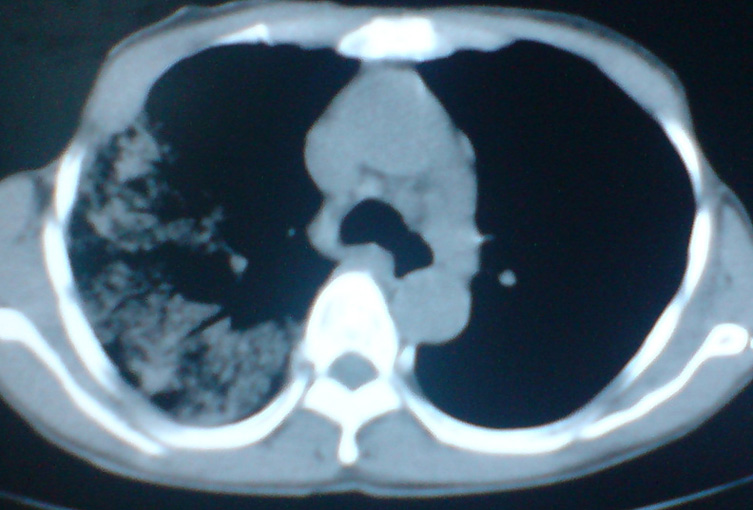

患者,女,60岁,右侧胸痛、咳嗽两个月。

干酪样肺炎?肺泡癌?请结合病史,有无发热、咳痰。

应首先考虑常规病变:大叶性肺炎,抗炎治疗后复查。补充病史及发全图像看看纵膈里面有无肿大的淋巴结。

考虑大叶性肺炎,抗炎治疗后复查或痰检除外肺泡癌。